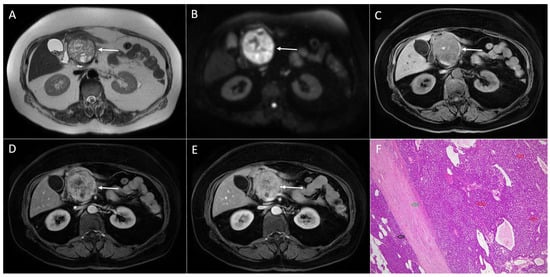

3.1. Neuroendocrine Tumors

3.3. Intrapancreatic Accessory Spleen